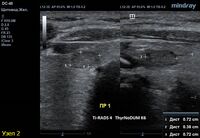

1) Узел занимает всю левую долю, но прорастает капсулу щитовидной железы (0 баллов), больше широкий чем высокий (0 баллов), не имеет кальцинатов (0 баллов), с ровным четким контуром (0 баллов), изоэхогенный (1 балл), тканевой структуры (2 балла). Количество баллов 3, ACRTi-RADS 3, ThyrNoDUMК3. Показана пункция в связи с большим диаметром узла (более 2,5см для Ti-RADS 3)